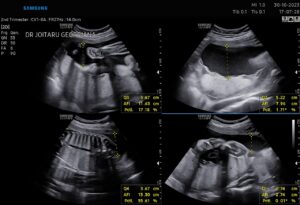

Fie ca vorbim despre biometria fetala sau monitorizarea Doppler, ecografia in sarcina ne furnizeaza cele mai importante informatii referitoare la starea de dezvoltare a bebelusului, si a anexelor( placenta, lichid) precum si starea de bine a mamei.(col uterin , ovare).

Morfologia de trimestrul II este una dintre cele mai spectaculoase ecografii. In cadrul acesteia evaluam cu foarte mare atentie dezvoltarea fiecarui organ in parte al bebelusului, si efectuam o serie de masuratori astfel incat sa verificam corespondenta cu normogramele international. Adica, verificam daca bebelusul se dezvolta armonios sau nu.

Intervalul de efectuare 22 de saptamani-24 de saptamani